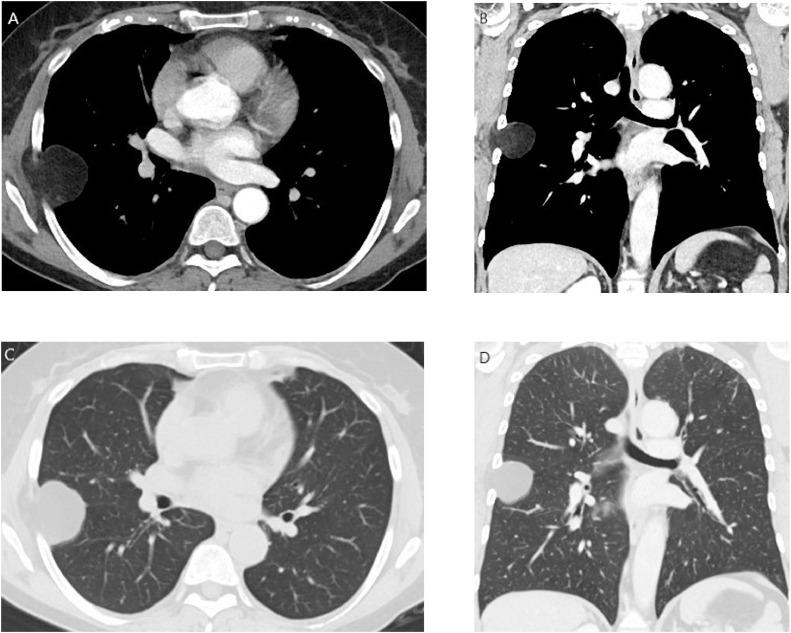

Lipoma is the most frequent benign soft-tissue tumor. It originates from fat cells. According to position, it is distinguished in superficial, typically subcutaneous lipoma, or deep, such as intramuscular lipoma. This latter form is infrequently and may resemble well-differentiated liposarcoma. For this reason, early radiological detection and characterization are necessary to obtain a wide complete resection and histopathologic evaluation to differentiate benign from malign lesions. We report an extremely rare case of an intrathoracic intramuscular lipoma of the chest wall detect and characterize with chest X-ray and computed tomography examinations, resected with thoracoscopic intervention and confirmed with histopathologic analysis.

脂肪瘤是最常见的良性软组织肿瘤。它起源于脂肪细胞。根据位置,可分为浅表性脂肪瘤,通常为皮下脂肪瘤,或深部脂肪瘤,如肌内脂肪瘤。后一种类型较为少见,可能类似于高分化脂肪肉瘤。因此,早期进行放射学检测和特征分析对于实现广泛的完整切除以及进行组织病理学评估以区分良性和恶性病变是必要的。我们报告了一例极其罕见的胸壁胸内肌内脂肪瘤病例,通过胸部X线和计算机断层扫描检查进行检测和特征分析,经胸腔镜干预切除,并经组织病理学分析确诊。